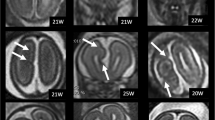

Examples of group A—bilateral asymmetric CFA as defined in this paper. Dysmorphic condition was defined as the clear abnormal distortion of profile of one or more lobes on both cortical and ventricular surface side, when present as dominant finding. Excessive gyration/sulcation was defined as the number of gyri/sulci of one or more lobes was higher than expected for gestational age, when present as dominant finding. Definitions of the other categories are self-explanatory. A1 (a)—axial and coronal images of a foetus (33 gestational weeks) with bilateral, asymmetric areas of dysmorphic brain (arrows). Other features recognised in this case were hypoplasia of the brainstem and cerebellum (not shown). A2 (b)—axial and coronal images of a foetus (23 gestational weeks) with bilateral asymmetric excessive sulcation/gyration (arrows). Cerebellar hypoplasia was also present. A3 (c)—axial and coronal images of a foetus (23 gestational weeks) with bilateral asymmetric shallow operculi (arrows). The foetus had severe hypogenesis of corpus callosum and unilateral mild ventriculomegaly. A4 (d)—axial and coronal images of a foetus (33 gestational weeks) with bilateral asymmetric trans-mantle clefts (arrows). The foetus had ventriculomegaly and was microcephalic. A5 (e)—coronal and sagittal images of a foetus (25 gestational weeks) with bilateral asymmetric multi-focal “bites” (arrows)

Examples of group B—bilateral symmetric CFA as defined in this paper. B1 (a)—axial and coronal images of a foetus (21 gestational weeks) with bilateral, symmetric areas of dysmorphic brain (arrows). Agenesis of the corpus callosum was also present. B2 (b)—axial and coronal images of a foetus (21 gestational weeks) with bilateral, symmetric excessive sulcation/gyration (arrows). B3 (c)—axial and coronal images of a foetus (30 gestational weeks) with bilateral, symmetric reduced sulcation/gyration (arrows). The foetus was microcephalic. B4 (d)—axial and coronal images of a foetus (27 gestational weeks) with bilateral, symmetric trans-mantle cleft (arrows). B5—there were no cases of bilateral symmetric multi-focal “bites” in the cohort. B6 (e)—axial and coronal images of a foetus (31 gestational weeks) with bilateral symmetric cobblestone cortex (arrows). Microphthalmia, abnormal brainstem (not shown) and ventriculomegaly were also present

Examples of group C—unilateral CFA as defined in this paper. C1 (a)—axial images of a foetus (25 gestational weeks) with a unilateral area of dysmorphic brain (arrows). There is abnormal low T2-weighted signal in the affected (left) hemisphere. The foetus also had agenesis of the corpus callosum and interhemispheric cyst. C2 (b)—axial and coronal images of a foetus (32 gestational weeks) with unilateral excessive sulcation/gyration (numerous, small gyri) in part of the left hemisphere (arrows). C3 (c)—axial and coronal images of a foetus (35 gestational weeks) with unilateral poor sulcation/gyration of the left hemisphere (arrows), that is hypoplastic. Unevenly diffuse reduced signal within white matter is present. The foetus also had a Dandy-Walker malformation (not shown). C4 (d)—axial and coronal images of a foetus (21 gestational weeks) with unilateral trans-mantle cleft in the left hemisphere (arrows). The cavum of septum pellucidum is absent. C5 (e)—axial and coronal images of a foetus (18 gestational weeks) with unilateral focal distortion in the form of an early abnormal sulcus in the left hemisphere (arrows). This foetus also had hypoplasia of the corpus callosum. C6 (f)—axial and coronal images of a foetus (26 gestational weeks) with unilateral enlarged right hemisphere (arrows), which is also generally malformed